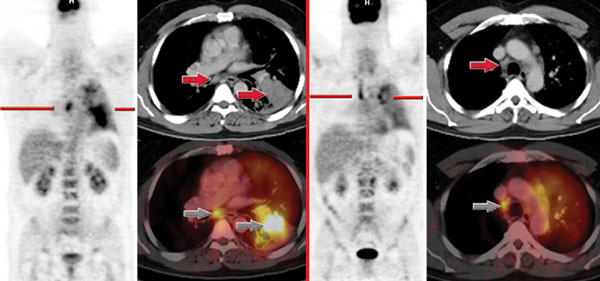

Đây quả là câu hỏi thú vị và rất có giá trị trong bối cảnh nhiều cơ sở y tế, đặc biệt là y tế tư nhân đã lạm dụng nhiều loại phương tiện chẩn đoán cận lâm sàng mau thu hồi vốn đãbỏ ra, tuy nhiên các chẩn đoán hình ảnh PET-CT lại có giá trị của nó. Theo các nhà chuyên môn cho thấy một kỹ thuật chẩn đoán ung thư mới có thể tìm kiếm các vị trí ung thư di căn, phát hiện tổn thương nguyên phát của ung thư, thậm chí phát hiện ung thư ngay khi cơ thể chưa hình thành tổn thương về mặt cấu trúc đã được đưa vào ứng dụng tại nhiều bệnh viện tuyến trung ương. Đó là tổ hợp thiết bị y khoa PET/CT và máy gia tốc Cyclotron. Đây là thiết bị y khoa hạt nhân áp dụng công nghệ kết hợp giữa máy PET và máy CT-scanner. Thiết bị này không chỉ có tác dụng trong lĩnh vực ung bướu mà còn giúp bác sĩ nâng cao chất lượng chẩn đoán và theo dõi nhiều loại bệnh khó trong các lĩnh vực khác như thần kinh, tim mạch. Đối với việc chẩn đoán và điều trị ung thư, việc ghi hình bằng PET/CT có thể giúp phát hiện ung thư giai đoạn sớm ngay sau khi cơ thể chỉ mới có sự thay đổi bệnh lý về chuyển hóa mà chưa hình thành tổn thương về mặt cấu trúc. Thiết bị còn giúp tìm kiếm các vị trí ung thư di căn, vị trí ung thư nguyên phát, giúp các bác sĩ tiên lượng các phương pháp điều trị hiệu quả hơn và đưa ra phác đồ điều trị bệnh lý cho bệnh nhân.

Trong khi đó, các phương pháp chẩn đoán hình ảnh khác như chụp cắt lớp vi tính, cộng hưởng từ, siêu âm chỉ phát hiện và đánh giá được các tổn thương khi đã có những thay đổi về cấu trúc giải phẫu ở mức độ đủ lớn và bỏ qua các tổn thương có đường kính dưới 1cm. Mặt khác, ở những bệnh nhân ung thư sau phẫu thuật, xạ trị, hóa trị, các tổn thương có thể biến dạng, thay đổi cấu trúc nên hình ảnh CT/ MRI vẫn có những hạn chế trong việc xác định các tổ chức còn sót tế bào ung thư, không phân biệt được các tế bào xơ hóa với tái phát và di căn. Cũng nhờ khả năng ghi nhận chính xác những bất thường PET/CT không những được dùng trong việc phát hiện sớm ung thư mà còn được dùng để đánh giá các phát triển của ung thư, sự di căn hay phát triển của ung thư tới các cơ quan khác của cơ thể hay sự tái phát của bệnh.

Như trên đề cập PET/CT là thiết bị y khoa hạt nhân áp dụng công nghệ kết hợp giữa máy PET và máy CT, có thể phát hiện được khoảng 80% các loại ung thư. Đối với việc chẩn đoán và điều trị ung thư, việc ghi hình bằng PET/CT có thể giúp phát hiện ung thư giai đoạn sớm ngay sau khi cơ thể chỉ mới có sự thay đổi bệnh lý về chuyển hóa mà chưa hình thành tổn thương về mặt cấu trúc. Đặc biệt thiết bị còn giúp tìm kiếm ở các bệnh nhân vị trí ung thư di căn, vị trí ung thư nguyên phát, giúp các bác sĩ tiên lượng và có nững phương pháp điều trị hiệu quả.

Nguyên lý cơ bản của kỹ thuật chụp PET/CT là ghi lại hình ảnh chuyển hóa trong tế bào (ở mức độ phân tử, mức độ tế bào). Sau đó hình ảnh ghi lại bằng máy PET/CT sẽ cho chúng ta thông tin về các thay đổi chuyển hóa của tế bào tổ chức (bằng máy PET), vừa xác định được vị trí chính xác của tổn thương (bằng máy CT). Để chụp PET/CT, bệnh nhân sẽ được tiêm tĩnh mạch một liều thuốc có phóng xạ positron, là một chất dẫn xuất glucose vì các tế bào ung thư sẽ hấp thụ và chuyển hóa nhiều glucose hơn các tế bào khác. Sau khi được tiêm thuốc có phóng xạ, cơ thể sẽ phóng ra các tua gamma và máy PET/CT sẽ tính toán từ các tua gamma này để thu nhập hình ảnh từ các tế bào khác nhau của cơ thể. Nhờ đó, những bất thường về chuyển hóa tại các tế bào sẽ được ghi nhận, ngay trước khi có sự thay đổi về cấu trúc.

Chụp PET/CT phát hiện được khoảng 80% các loại ung thư và hỗ trợ việc đánh giá hiệu quả của các phương pháp điều trị. Những bệnh nhân có nguy cơ cao đối với ung thư hoặc những bệnh nhân sau khi thử gen, thử máu phát hiện một số chỉ điểm về ung thư thì nên chụp PET/CT để kiểm tra. PET/CT có thể phát hiện được khoảng 80% các loại ung thư vì việc tăng sinh hoạt động với glucose là phổ biến ở các tế bào ung thư, tuy nhiên, cũng có một số tế bào ung thư không tăng sinh hoạt động với glucose, chỉ tăng sinh hoạt động chuyển hóa chất khác như mỡ, đạm, thì có thể khó phát hiện.